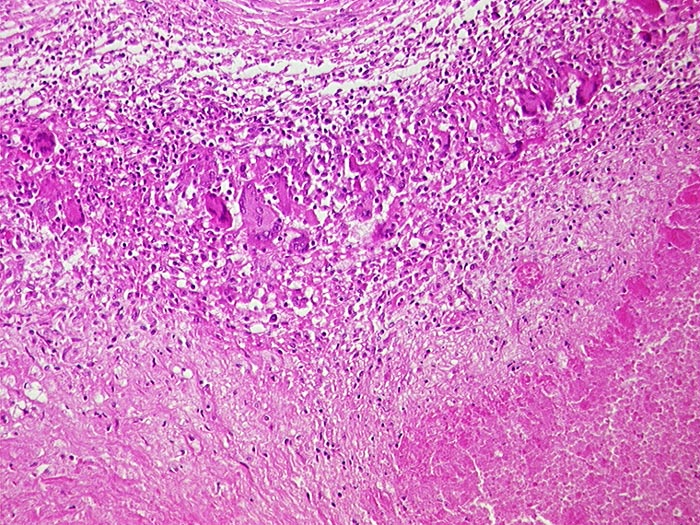

PathoPic ID 726 - Atypische Mykobakteriose

Atypische Mykobakteriose

Entzündung infektiös

Lymphknoten, abdominal

Lymphatische Gewebe, KM, Milz

Mesenteriale Lymphknoten mit verkäsenden Granulomen aus Epitheloidzellen und Riesenzellen.

Nachweis von Mycobacterium avium intracellulare

AIDS. HIV Positivität bekannt seit 2 Jahren bei iv Drogenabusus. Pneumocystis carinii Pneumonie.

Histologie